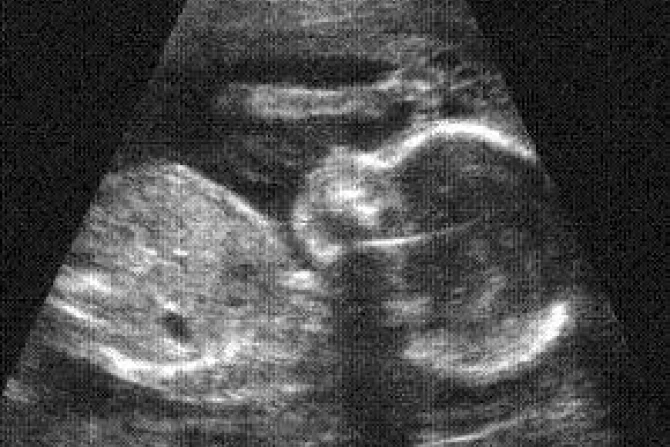

Some doctors and pro-life leaders now say ultrasound technology is partly responsible for Americans’ gradual shift to identifying themselves as pro-life. Nebraskan legislators are now considering joining the many states which require that a woman considering an abortion be provided an ultrasound of her baby.

"Ultrasound used to be less available, very grainy. Now the baby is very clear, very distinct," Charmaine Yoest of Americans United for Life told Fox News.

Massachusetts Doctor Eric J. Keroack reported to Fox News that a two-year study showed 75 percent of his patients who were unsure about having an abortion decided not to after choosing to view the ultrasound images of their child.